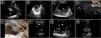

Ultrasound-guided pericardiocentesis. A) Subcostal 4 chamber view. B) Parasternal long-axis view. C) Apical view. As noted, the optimal window to insert the needle is the apical, given the shorter distance to reach the pericardial space (continuous green line) and higher pericardial fluid thickness (continuous yellow line). RA, right atrium; RV, right ventricle; LA, left atrium; LV, left ventricle; RVOT, right ventricular outflow tract. Asterisks indicate pericardial effusion. Adapted from Blanco P, Figueroa L, Menéndez MF, Berrueta B. Pericardiocentesis: ultrasound guidance is essential. Ultrasound J. 2022;14(1):9. https://theultrasoundjournal.springeropen.com/articles/10.1186/s13089-022-00259-5. (CC-BY-4.0). D) Recognition of the left internal thoracic vessels along the left parasternal line (dotted white line) with a linear probe on two-dimensional and color Doppler imaging; s-sct, skin-subcutaneous tissue; m, intercostal muscle; r, rib; arrowhead, pleura; asterisks, internal thoracic vessels. E) Recognition of the intercostal vessels with a linear probe on color Doppler imaging. Real-time in-plane ultrasound-guided pericardiocentesis via intercostal approach (apical view) using a linear probe. The needle (arrows) is entirely observed in the pericardial space (asterisks); LV: left ventricle. G) Hemorrhagic fluid is freely evacuated from the pericardial space after catheter placement.

PreprocedureA convex or a phased-array probe is used to assess the view where the effusion accumulation is maximal and closest to the transducer. The thickness of the effusion is measured in diastole in each window, while the distance from the skin to the parietal pericardium and to the myocardium (visceral pericardium) should be obtained to estimate the needle depth of insertion and needle length (Fig. 2A–C). Qualitative assessment should also be performed. While anechoic fluid can be either a transudate or an exudate, the presence of debris or septations points towards the latter. Quantitative and qualitative assessments aid in decision making regarding whether pericardiocentesis, another procedure, or no procedure should be performed. Using a linear probe, the pleura, internal thoracic vessels, and intercostal vessels are delineated to exclude these structures from the needle trajectory (Fig. 2D, E.50